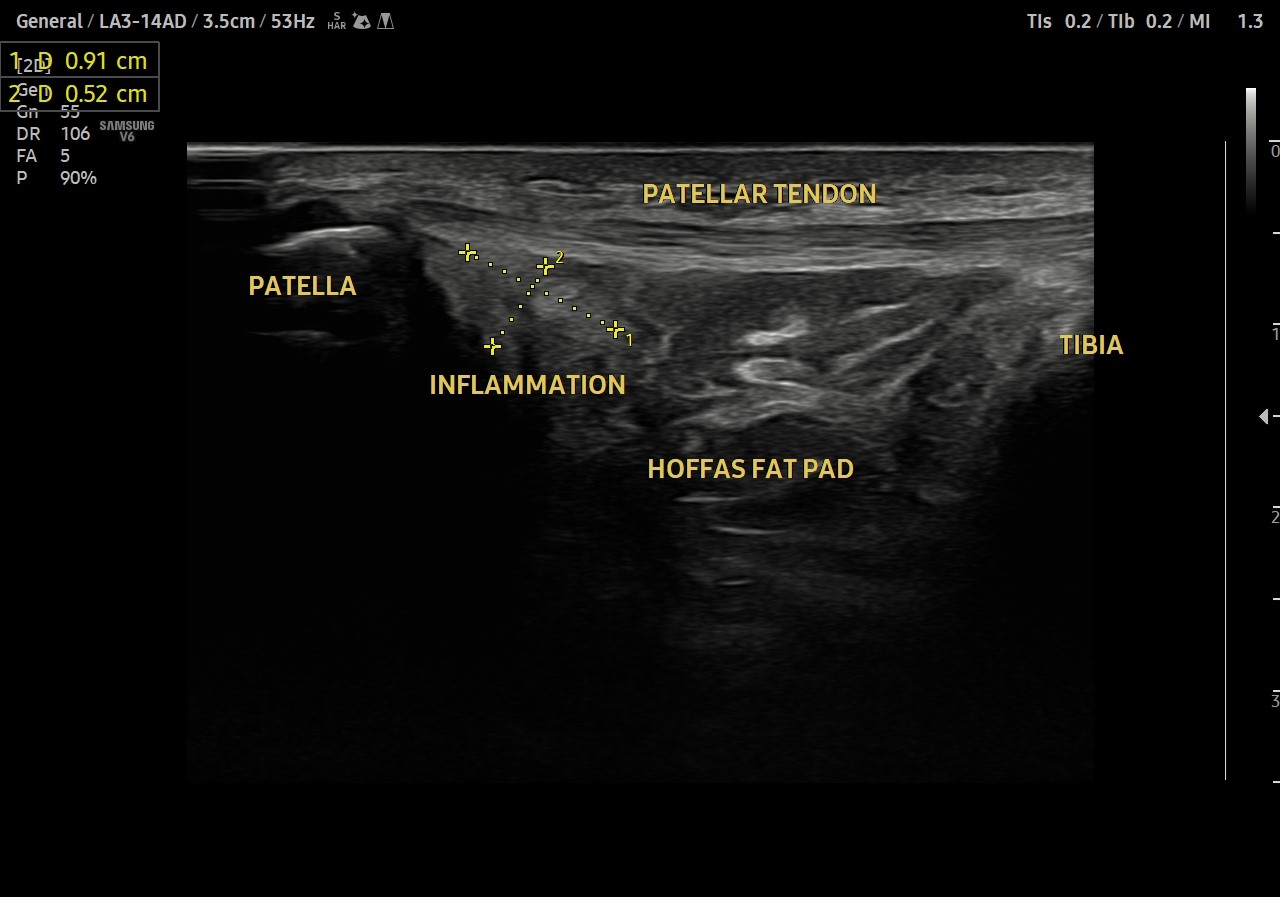

Patellar fat pad impingement

Case of Hoffas fat pad impingement between Patellar tendon and lateral femoral condyle